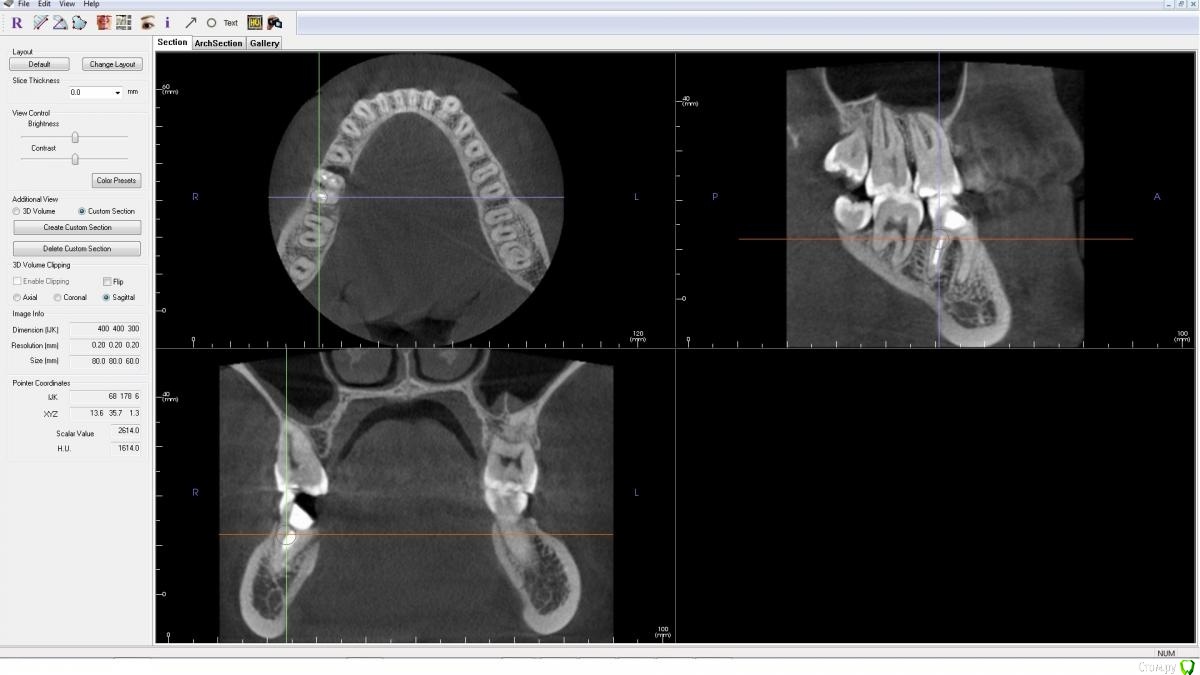

AlenaDM Опубликовано 17 февраля, 2021 Поделиться Опубликовано 17 февраля, 2021 (изменено) Добрый день.Сильно разрушен зуб. Ищу варианты протезирования. Уже посетила нескольких врачей, у всех вариант один - удаление и установка импланта, но возможно кто-то сможет помочь/подсказать другой вариант так сказать, можно ли обойтись "меньшей кровью".КТ из клиники прилагаю (открывается, к сожалению, только в Windows 8 и ниже, формат .exe)Спасибо!https://drive.google.com/file/d/1J0UHeSeCaEhpX65WpDZoImWtN_fYxXUO/view?usp=sharing Изменено 17 февраля, 2021 пользователем AlenaDM Ссылка на комментарий

wladdX Опубликовано 17 февраля, 2021 Поделиться Опубликовано 17 февраля, 2021 На мой взгляд показано удаление. Ссылка на комментарий